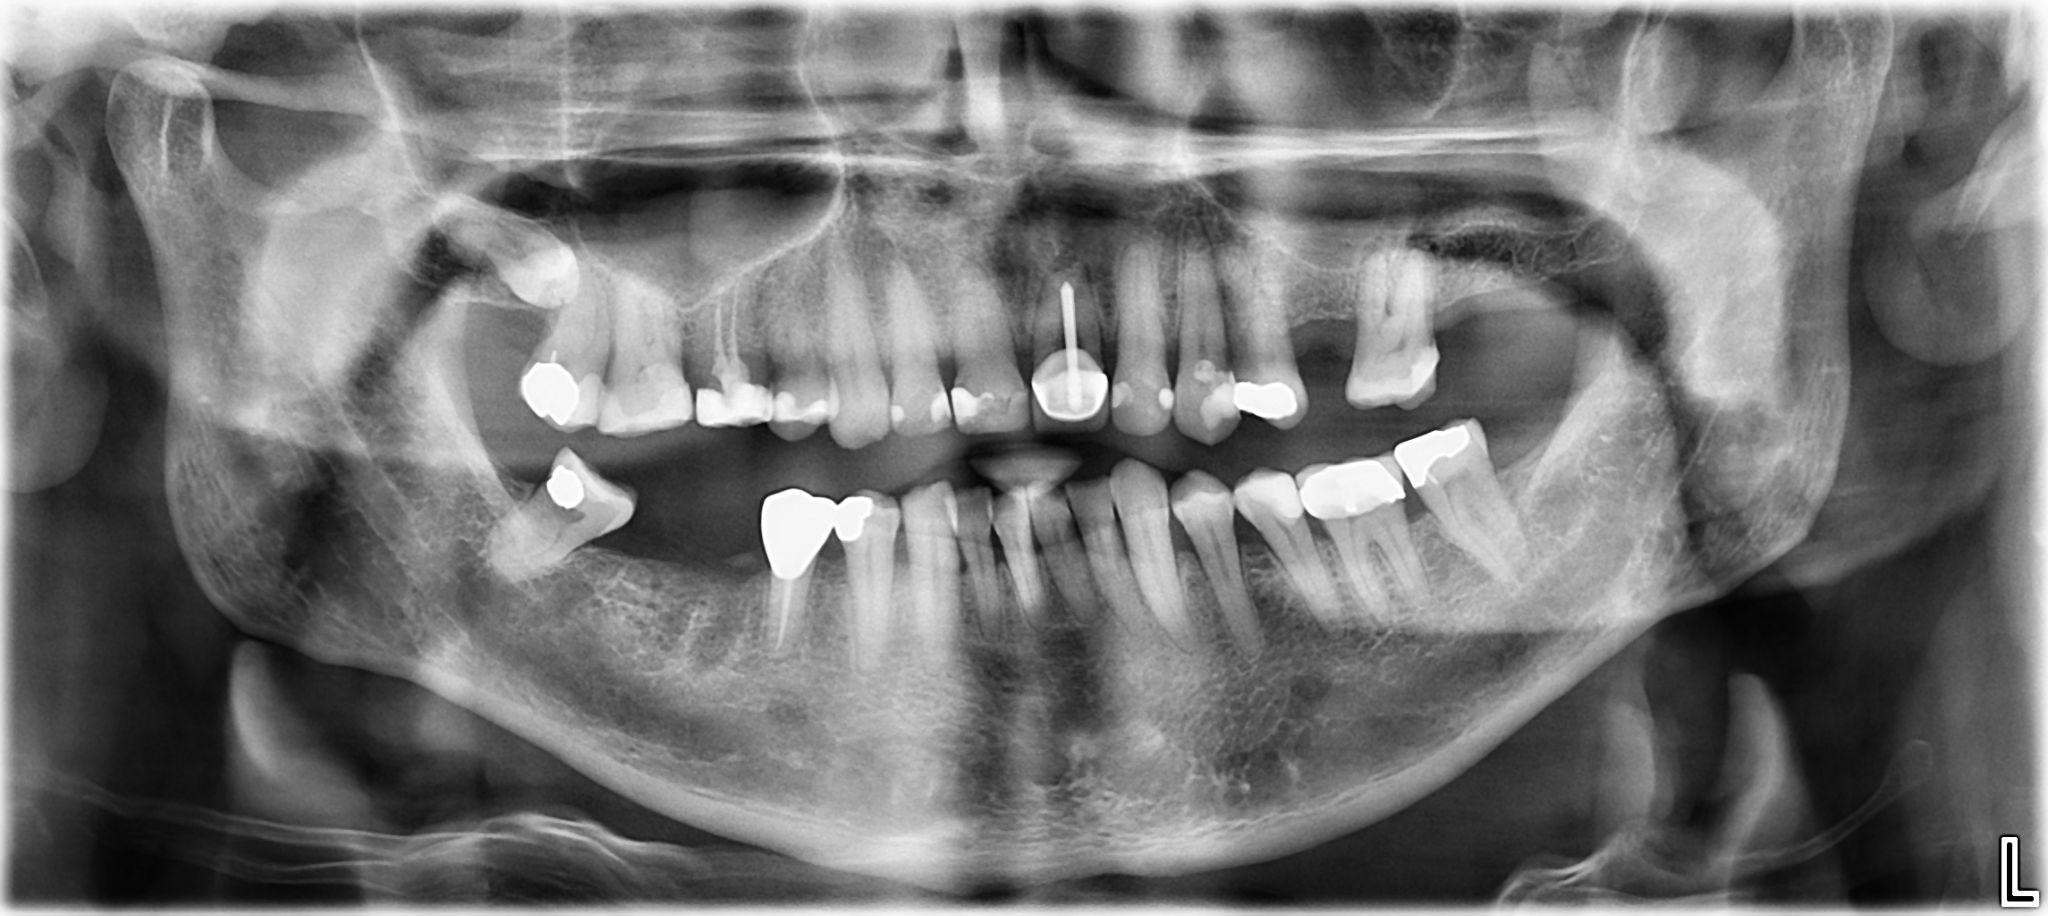

16. What option cannot be selected for the upper jaw of this panoramic X ray?

17. What option cannot be selected for the lower jaw of this panoramic X ray?

18. What option cannot be selected for the upper jaw of this panoramic X ray?

19. What option cannot be selected for the lower jaw of this panoramic X ray?

20. What option can be selected for the upper jaw of this panoramic X ray?

21. What option cannot be selected for the lower jaw of this panoramic X ray?

22. What option cannot be selected for the upper jaw of this panoramic X ray?

23. What option cannot be selected for the lower jaw of this panoramic X ray?

24. What option cannot be selected for the upper jaw of this panoramic X ray?

25. What option cannot be selected for the lower jaw of this panoramic X ray?